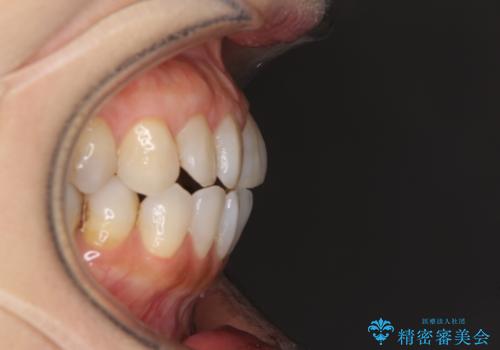

前歯の突出感と上下の隙間 インビザラインによる矯正治療

- 前歯の上下スペースと前歯の隙間を気にして来院された患者様です。

インビザラインにより上下の前歯の隙間を閉じながら、IPRを用いて口元の突出感を合わせて改善していくこととしました。

上下の隙間に舌が入り込むことが、すきっ歯やオープンバイトの原因であったため、舌の筋肉のトレーニングも並行して行い、後戻りの抑制を図りました。